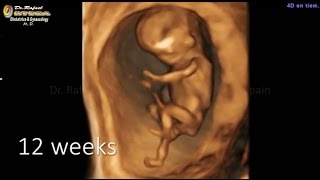

4D ultrasound performed in the Ultrasound Unit of the Gynecological Clinic Dr. Rafael Ortega Muñoz in which a fetus of 12 weeks 4D shows moving and jumping impressive

4D ultrasound pregnancy of 12 weeks fetus moving dancing Gynecologist